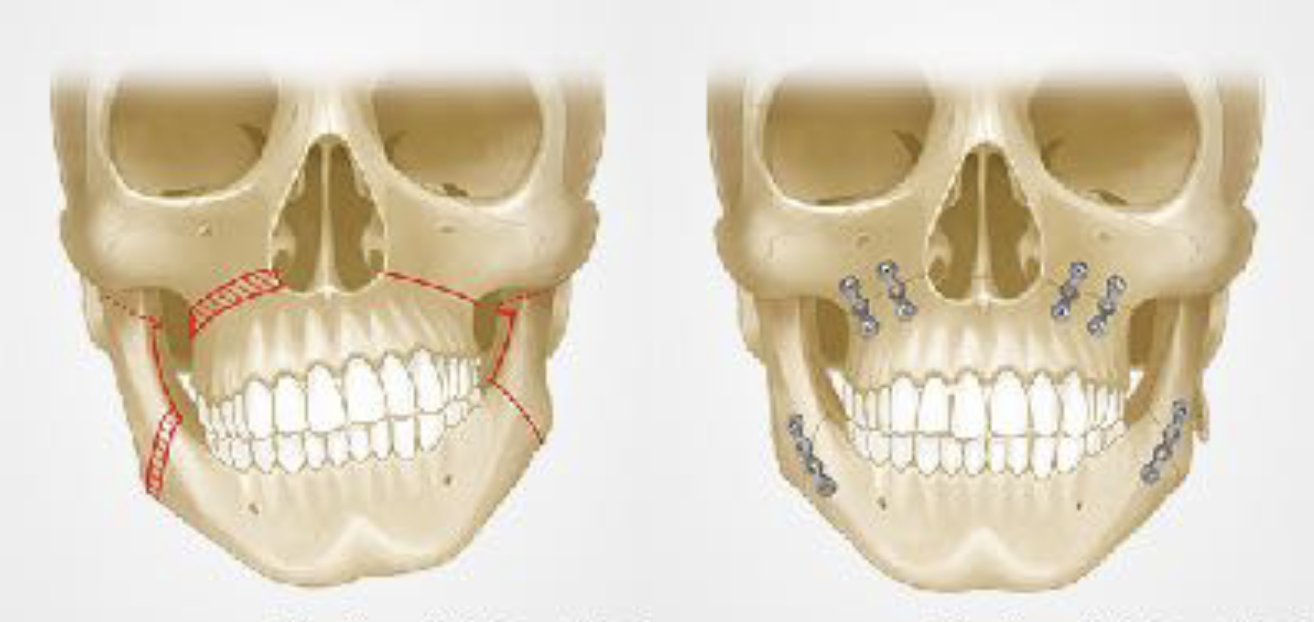

顎変形症とは、上下の顎の位置や形に問題があり、かみ合わせが大きくずれている状態を指します。この状態を放置すると、食べ物をうまく噛めない、発音が不明瞭になるといった機能的な問題に加えて、顎関節の痛みや不快感、お顔の歪みなど、さまざまなトラブルが生じることがあります。治療は外科矯正治療を含む骨切り手術が必要となります。

左上図は受け口(下顎前突)の骨格(クラスⅢ)。

骨切り手術により下図のような上下顎がバランスのいい状態へ変化させることができます。

左上左図は受け口の逆で下顎が小さい骨格(クラスⅡ)。

SSROという骨切り手術によって上下顎のバランスを良くすることができます。

上顎骨が斜めに傾いてる症例も問題があります。

ルフォーという骨切り手術でゆがみを治すことができます。

上顎骨にルフォー、下顎にSSROを行ったイメージ図です。